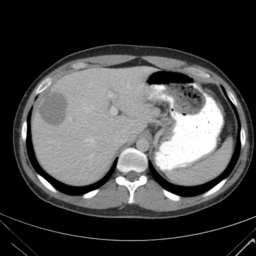

![]() |

| (a) | (b) | (c) | (d) |

Unsupervised Categorization: Our category discovery clusters are generally visually coherent within the cluster and size-balanced across clusters. However, image clusters formed only based on text information (of radiology reports) are highly unbalanced [49], with three clusters inhabiting the majority of images. Note that our method imposes no explicit constraint on the number of instances per cluster. Fig. 6 shows sample images and their top-10 associated key words from two randomly selected clusters (more results are provided in the supplementary material). The LDPO clusters are found to be clinically or semantically related to the corresponding key words, which describe presented anatomies, pathologies (e.g., adenopathy, mass), their associated attributes (e.g., bulky, frontal) and imaging protocols or properties.

The category discovery clusters employing our LDPO method are found to be more visually coherent and cluster-wise balanced in comparison to the results in [49] where clusters are formed only from text information ( radiology reports). Fig. 7 Left shows the image numbers for each cluster from the AlexNet-FC7-Topic setting. The numbers are uniformly distributed with a mean of 778 and standard deviation of 52. Fig. 7 Right illustrates the relation of clustering results derived from image cues or text reports [49]. Note that there is no instance-balance-per-cluster constraints in the LDPO clustering. The clusters in [49] are highly uneven: 3 clusters inhabit the majority of images. Fig. 6 shows sample images and top-10 associated key words from 5 randomly selected clusters (more results in the supplementary material). The LDPO clusters are found to be semantically or clinically related to the corresponding key words, containing the information of (likely appeared) anatomies, pathologies (e.g., adenopathy, mass), their attributes (e.g., bulky, frontal) and imaging protocols or properties.